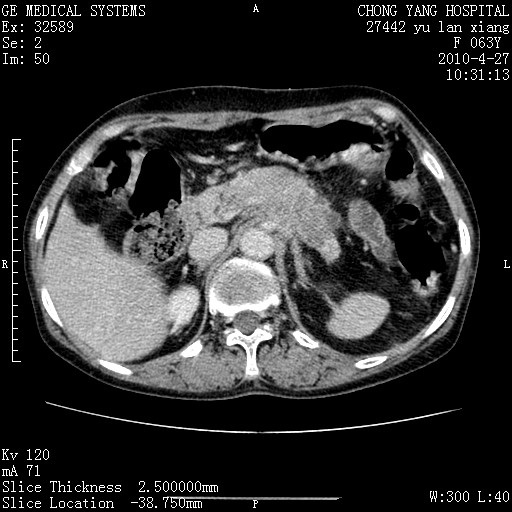

标题: CT26066:F63Y 上腹正中压痛半月,CA199:7400u/ml,MR示胰腺炎伴 [打印本页]

胰腺癌侵犯腹腔动脉干-分支、胃壁、左侧膈肌伴胰周及腹膜后淋巴结转移、胆囊切除术后。

胰腺癌侵犯腹腔动脉干-分支、胃壁、左侧膈肌伴胰周及腹膜后淋巴结转移、胆囊未显影。